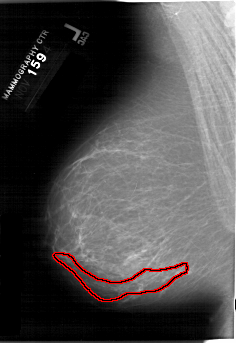

FILE: A_1202_1.LEFT_MLO.OVERLAY

TOTAL_ABNORMALITIES 1

ABNORMALITY 1

LESION_TYPE CALCIFICATION TYPE PLEOMORPHIC DISTRIBUTION SEGMENTAL

ASSESSMENT 5

SUBTLETY 3

PATHOLOGY MALIGNANT

TOTAL_OUTLINES 1

BOUNDARY